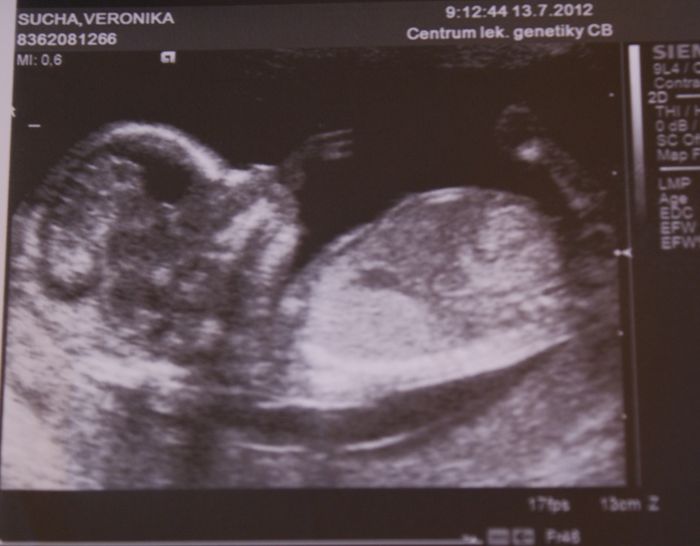

Teda koukám, že se u těch fotek při rozbalení píšou spřeházený názvy, ta první je ze 14.týdne, druhá je focená před chvilkou, moje bříško dnes 20.týden a třetí z UZ ze včera 20.týden mimísko

A jinak je to fakt asi pohodář, protože jak ve 14.týdnu tak včera při UZ měl jednu ruku za hlavou